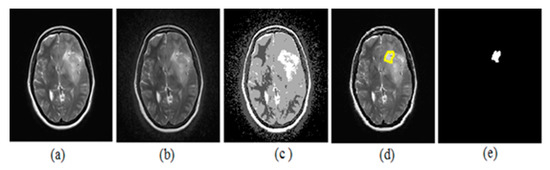

The upcoming figures are sectioned into three parts: Each part has an original neonatal brain image, and segmentation is achieved on that image. All the sections were subdivided into two parts—a and b. Part ‘a’ helps in visualizing tumor detection over the original image (which is not enhanced). On the other hand, part ‘b’ is of the enhanced image. Figure 10 represents the (a) original image, (b) preprocessed with BPDFHE enhanced image, (c) segmentation result using the median filter, (d) detection of the tumor, and (e) extraction of the tumor using thresholding.

Figure 10.

(a) Original image, (b) BPDFHE enhanced image, (c) segmentation result using median filter, (d) detection of tumor, and (e) extraction of tumor using thresholding.

The estimation of the proposed hybrid method for preprocessing and segmentation using a machine learning algorithm was shown on various MRI images to detect tumors. We placed the images for better visibility after simulations in ink space were used.

Justification of the results was carried out with the dice index (DI) and Jaccard index (JI). The ground truth (GT) image was considered to estimate the performance, which was prepared with the help of a radiologist.

The proposed ARKFCM technique considers spatial information of pixels for processing images which are affected by artifacts such as noise and intensity in-homogeneities. Hence, this procedure includes the effect of neighborhood pixels/voxels aimed at spatial information. Thus, it is capable of extracting boundaries in a proper way when compared to the existing, conventional FCM technique. It was witnessed that the implemented method was able to classify the effects of shielding and bright variations. Therefore, in brief, the main advantages of the proposed method were identified as robust to noise and shielding effects. The computable calculation was performed with Dice Index (DI) and Jaccard Index (JI) metrics [33], processing the difference between the segmented and GT images.

Segmentation results of the proposed method are shown in Figure 11 and Figure 12. The obtained numerical values are tabulated in Table 5 and Table 6 respectively, including the performance measures of dice similarity and Jaccard index. The proposed method provides efficient and robust results when compared to the FCM technique by a mean of a 98.86% dice index and 96.9% Jaccard index. This helps the physician to check whether the presence of any abnormalities is available in the MRIs corresponding to different parts of the brain. We conclude that the proposed remodified FCM technique ARKFCM method is more robust to noise and shading effects; the major advantage of using this technique is locating the tumor and affected regions.